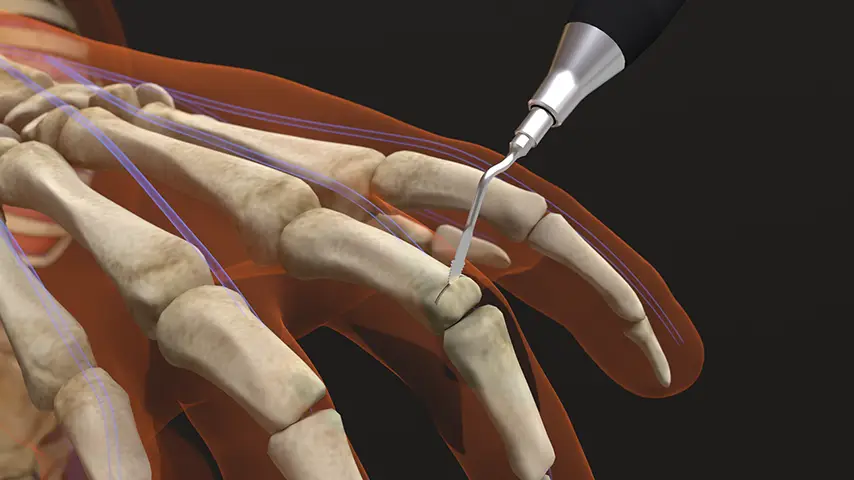

in Hand Surgery

Interphalangeal Joint Arthrodesis

Details

PIEZOSURGERY® allows a controlled and extremely clean preparation of joint surfaces, improving the stability of the fusion while preserving surrounding soft tissues. This is particularly valuable in small, fragile bones where precision is critical.

Recommended insert: